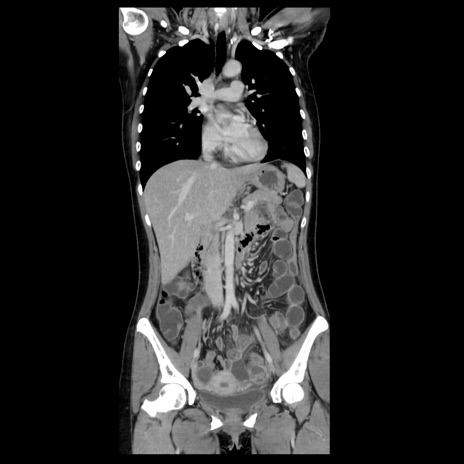

症例39(冠状断像)

【症例】40歳代女性

【主訴】上下腹部痛

【現病歴】2日目から下腹部痛あり。夜間は痛みで眠れなかった。昨日より上腹部痛と下痢が出現。臥位で痛みは軽快したため、休んでいた。本日になって臥位でも立位でも痛みが強くなってきたため救急要請。

【既往歴】子宮内膜症

【身体所見】部:平坦・軟、左上下腹部に圧痛あり、反跳痛あり。

【データ】WBC 21800、CRP 26.78

CT